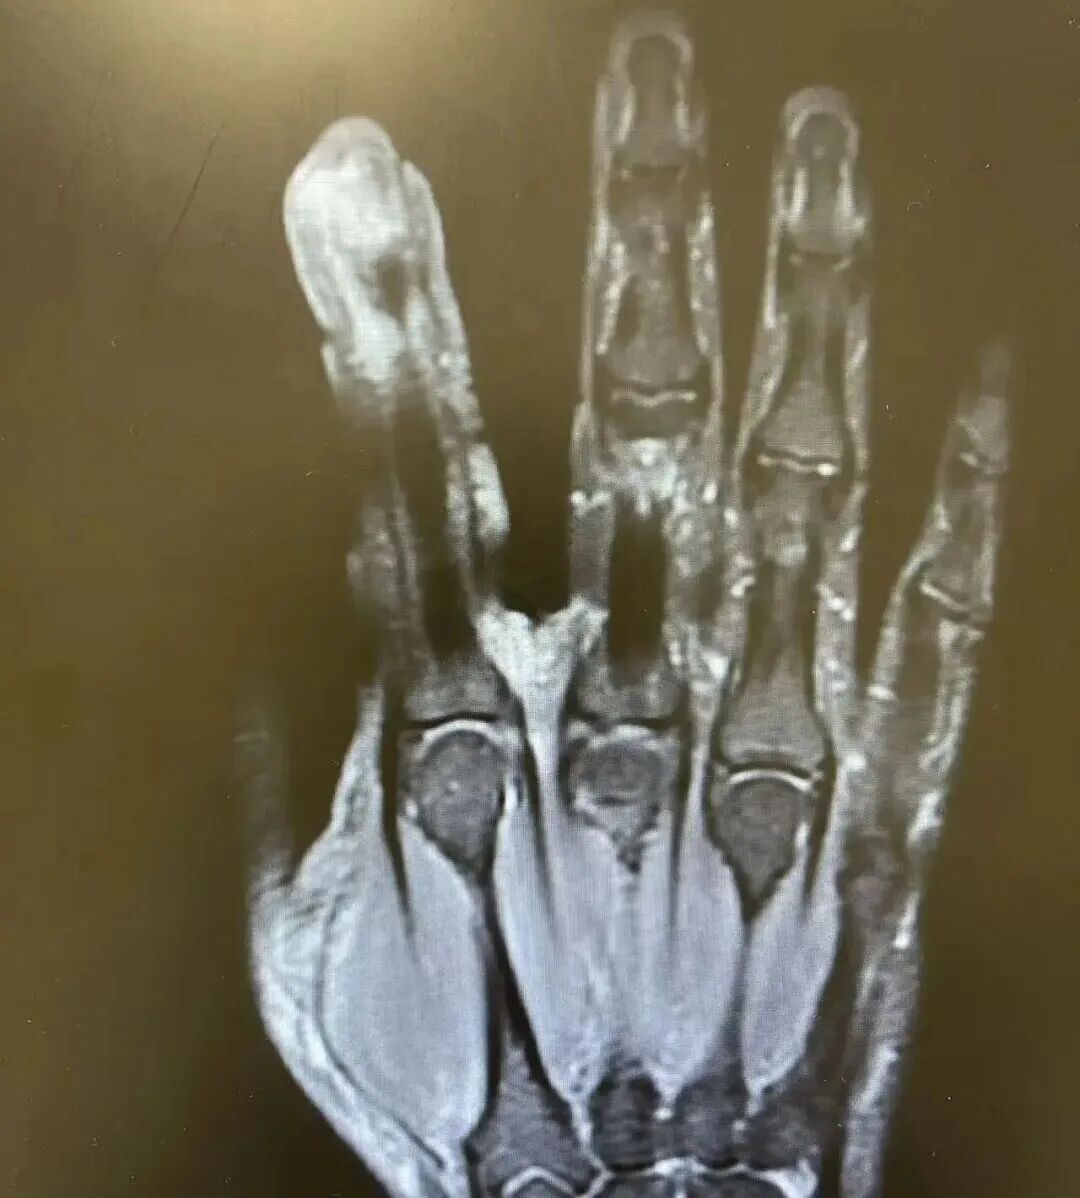

经查验,李苍老破溃的左手指尖严重感染,厌氧消化链球菌顺着禁锢处钻到骨头里,激发了严重骨髓炎。医师蹙迫手术,帮李苍老“刮掉”坏死的骨头碎屑,破除了坏死的肌肉与皮肤。